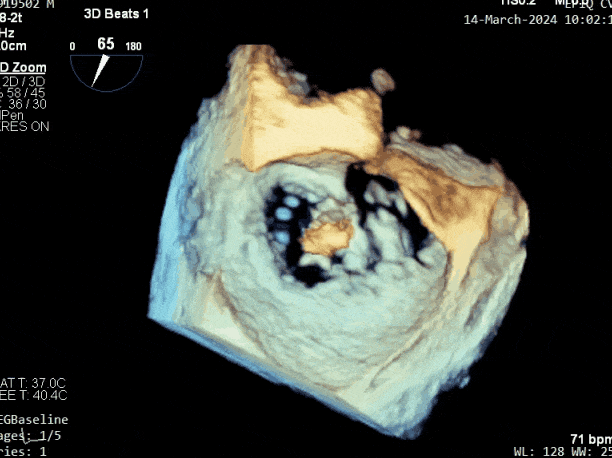

二尖瓣后叶活动受限,呈房源性栓系,以P3区为重,二尖瓣前叶假性脱垂,二尖瓣瓣环前后径49mm,左右径40mm。

PISA法测r=12mm,EROA=0.72cm2,RVOL=100ml,RF 26%。LVEDD 57mm,左房71*59*77mm,右房55*69mm,LVEF 70%。

二尖瓣反流(重度,4+级,Carpentier I型)